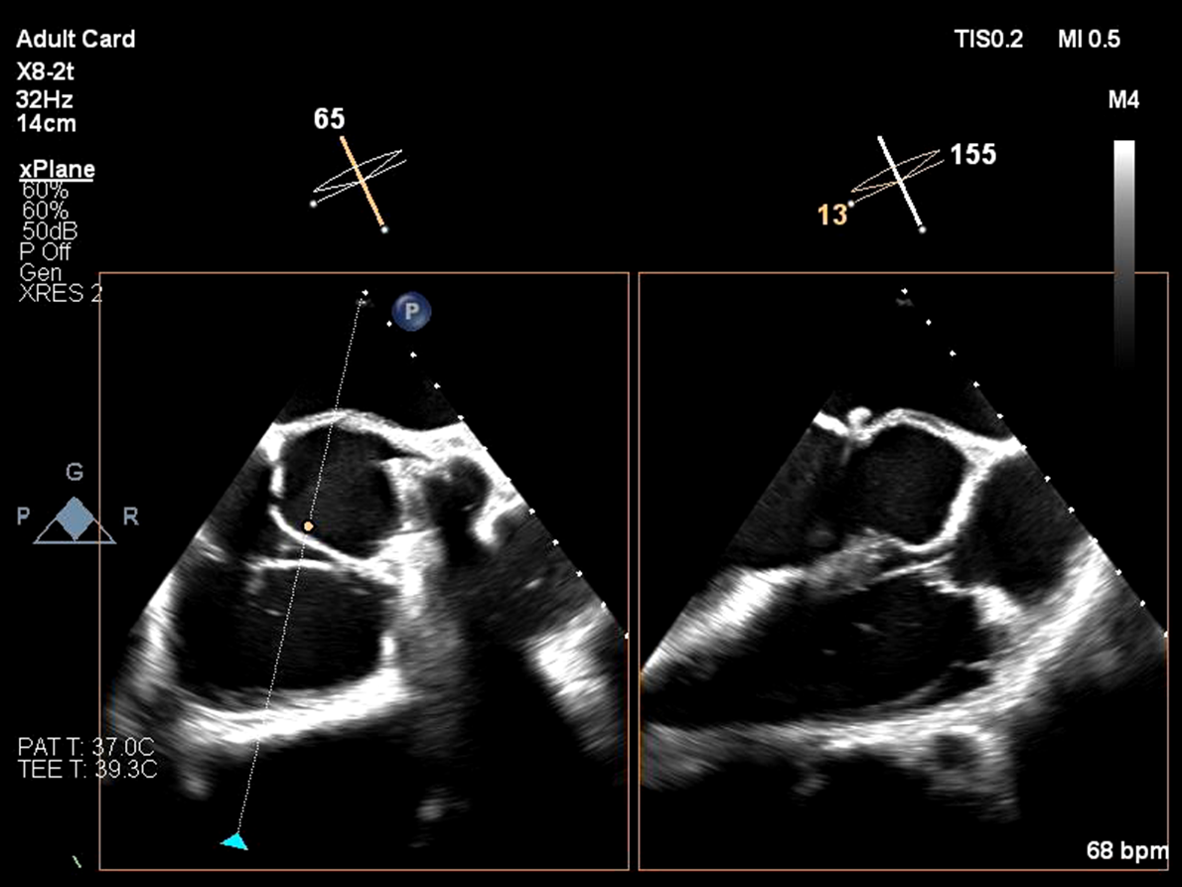

Relevant Test Results Prior to Catheterization

EKG showed normal sinus rhythm with ST segment elevation at V1-3 , inverted T wave at V4-6 , I ,aVL. Echocardiogram showed impaired LV systolic function, global wall hypokinesia, normal prosthetic aortic valve function with mild paravalvular leakage and bulging of aortomitral intervalvular fibrosa, suspected Aortomitral intervalvular fibrosa aneurysm. CT cardiac revealed pseudoaneurysm of the aortomitral intervalvular fibrosa with laminated thrombus with no LAA thrombus visualized.